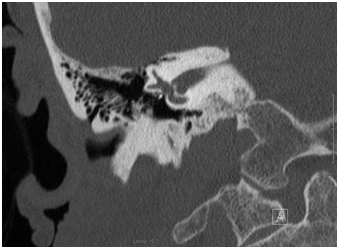

He was advised of the potential etiologies for sudden SNHL. Although the favored mechanism of loss was the result of a forceful and sudden lateralization of the stapes prosthesis, resulting in a PLF, surgical intervention was not encouraged given the duration of the deafness and the spontaneous resolution of the dizziness. Other etiologies were also considered. Therefore he did begin a course of high dose oral prednisone. A high resolution Temporal bone CT scan was obtained. Representative images are shown Figures 2 & 3. While not definitive, these did appear to show lateral displacement of the stapes piston. He returned to the office 1week later with no improvement in his hearing. The steroids were discontinued. His dizziness continued to resolve.

Figure 3 Coronal Temporal bone CT. This image depicts the medial-most position of the prosthesis in the coronal plane.